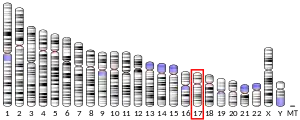

| External IDs | OMIM: 612912 MGI: 1916321 HomoloGene: 6443 GeneCards: TMEM97 | ||||||||||||||||||||||||||||||||||||||||||||||||||

- 1 2 3 GRCh38: Ensembl release 89: ENSG00000109084 - Ensembl, May 2017